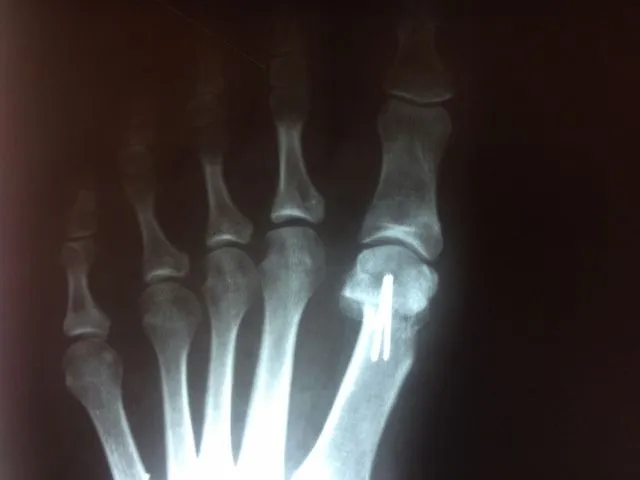

In the x-ray image below is a Hallux Valgus or what is more commonly known as a bunion deformity where the great toe is deviated towards the lesser toes causing abnormal structure which is a result of genetics, abnormal shoegear and abnormal mechanics will cause wearing of the joint and enlargement of the head of the long bone called the first metatarsal.

Post-surgical repair of the same patient bunion deformity with the great toe now in rectus (straight) position with surgically placed screws in the head of the first metatarsal that were used to secure fixation of the cut made across the bone to translate the head of the bone laterally in order to reduce the deformity. The screws will remain in place even after the bone heals.